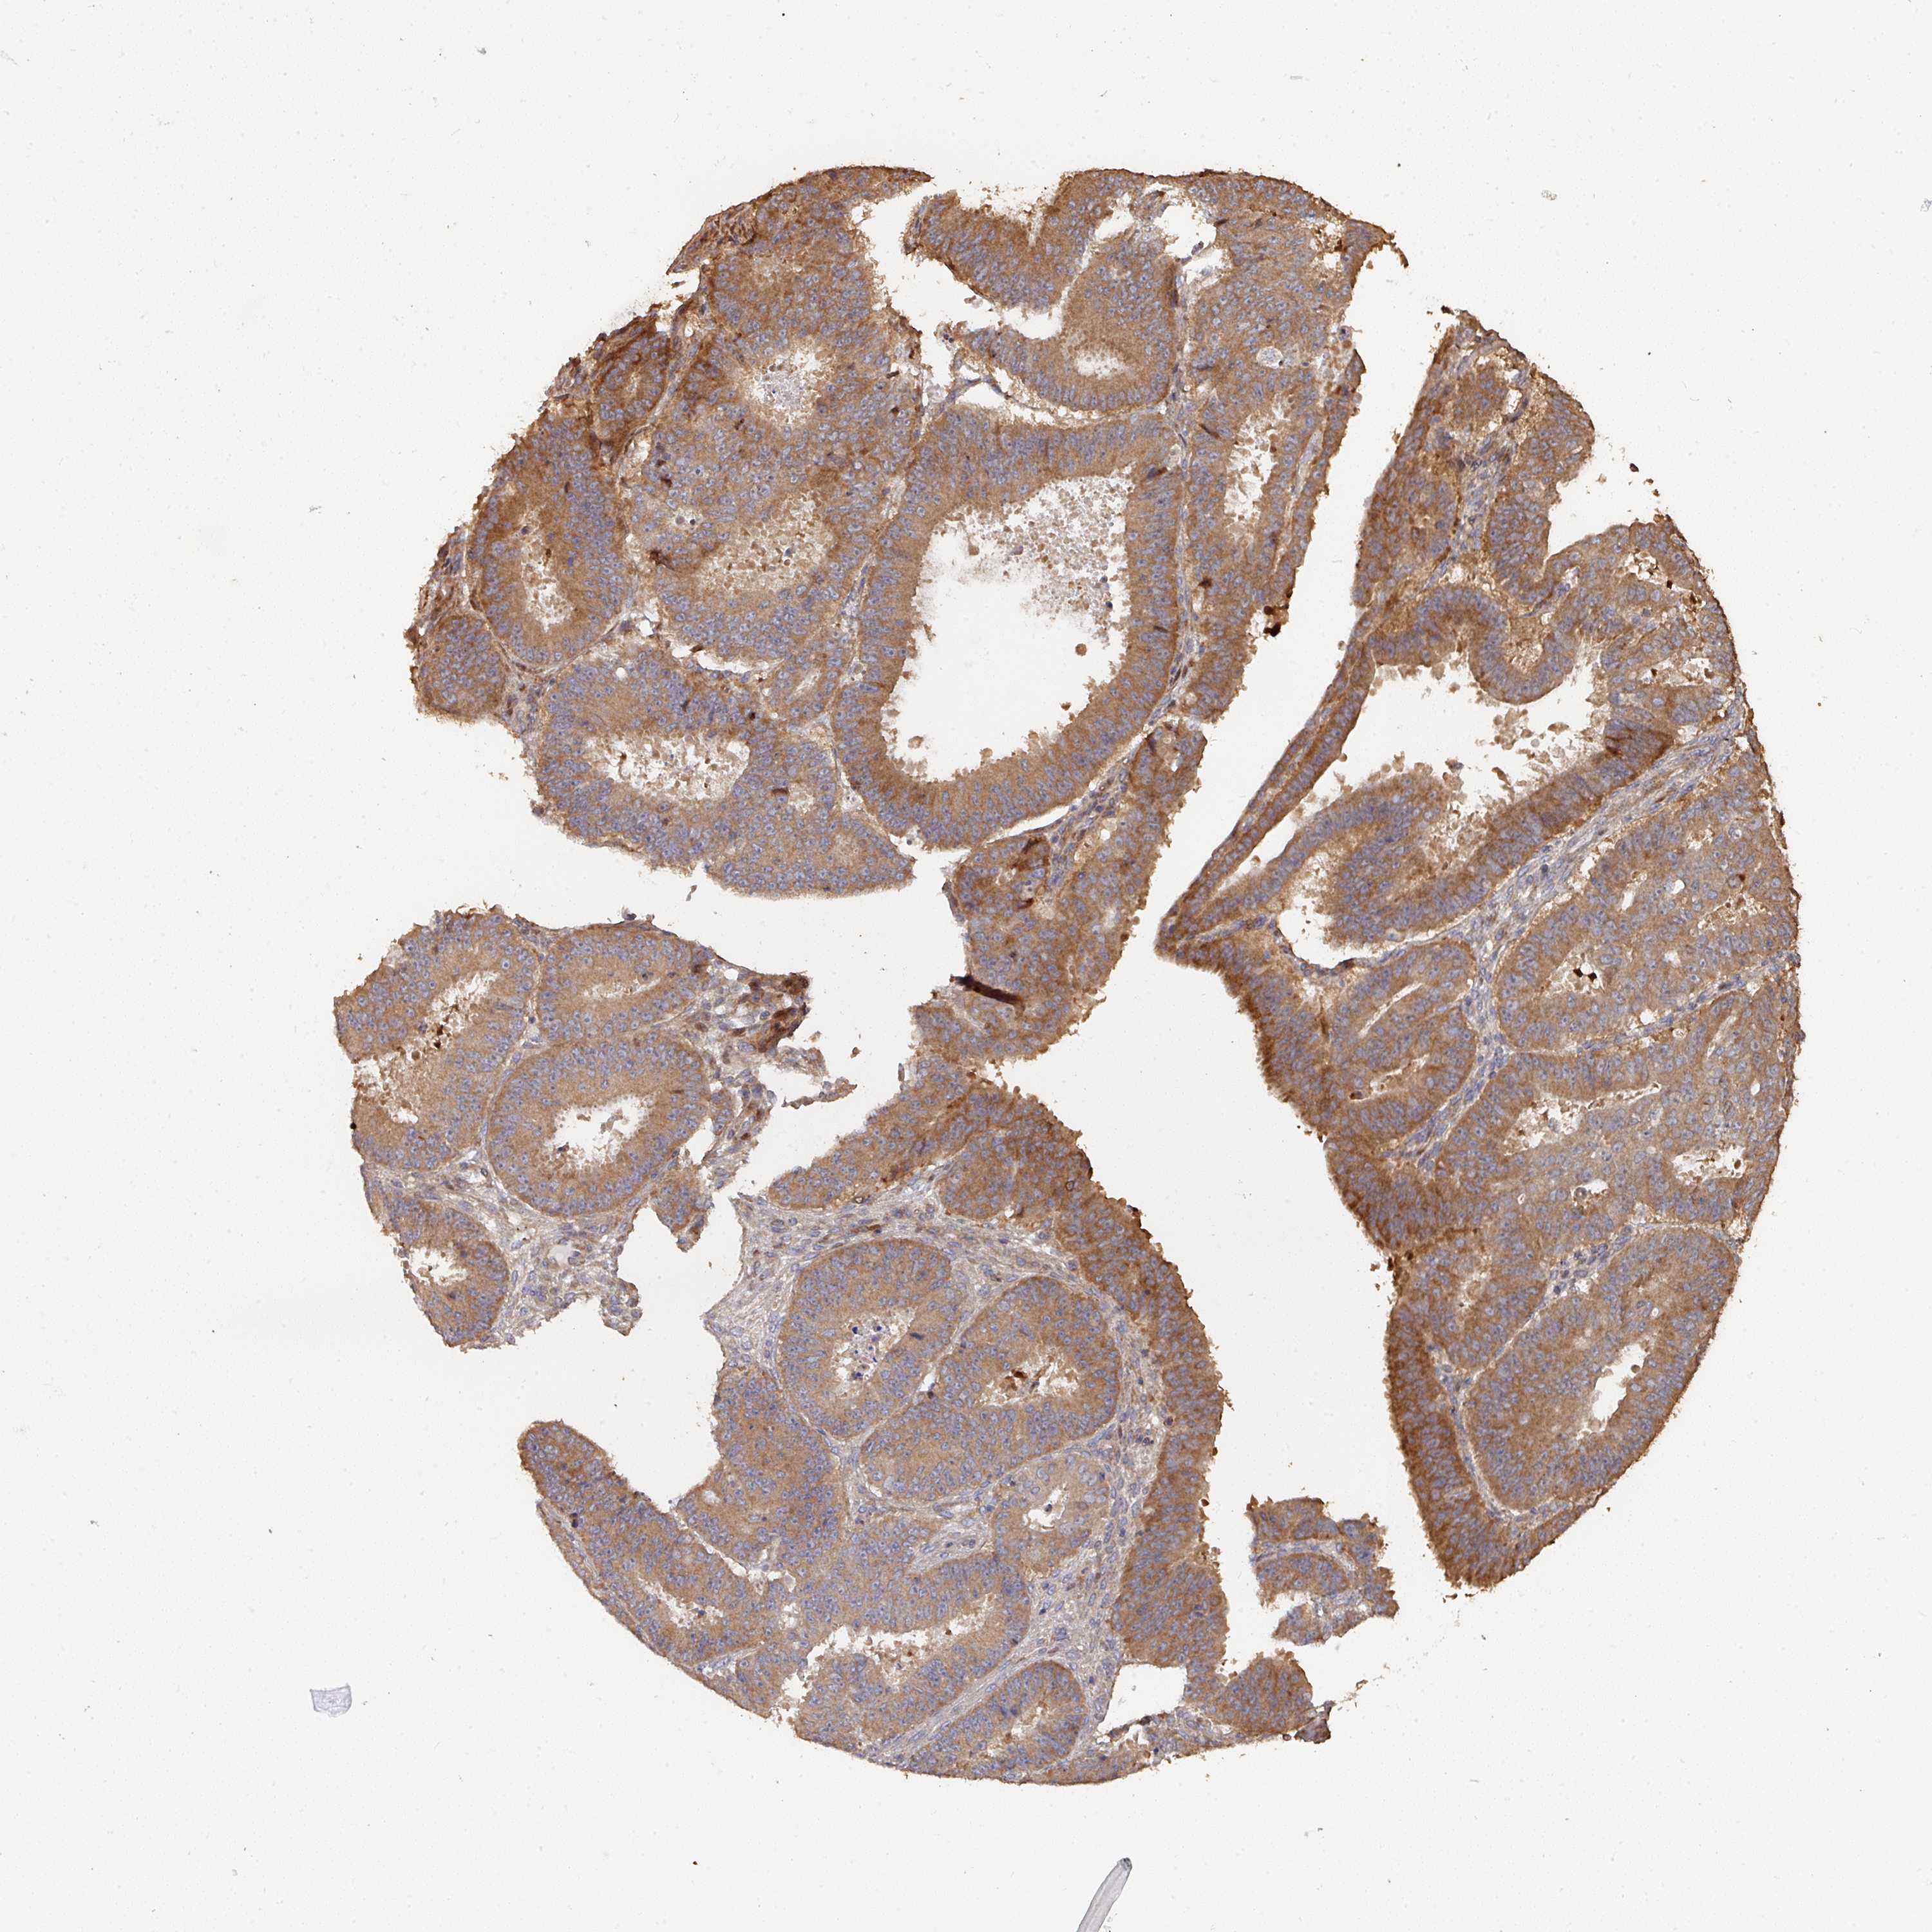

OVARIAN CANCER - Protein expressioni

A mouse-over function shows sample information and annotation data. Click on an image to view it in a full screen mode. Samples can be filtered based on level of antibody staining by selecting one or several of the following categories: high, medium, low and not detected. The assay and annotation is described here.

Note that samples used for immunohistochemistry by the Human Protein Atlas do not correspond to samples in the TCGA dataset.

Antibody stainingi

Antibody staining in the annotated cell types in the current human tissue is reported as not detected, low, medium, or high, based on conventional immunohistochemistry profiling in selected tissues. This score is based on the combination of the staining intensity and fraction of stained cells.

Each image is clickable and will lead to virtual microscopy that enables deeper exploration of all samples and also displays staining intensity scores, fraction scores and subcellular localization as well as patient and tissue information for each sample.

Antibody HPA047237

Staining

High

Medium

Low

Not detected

Intensity

Strong

Moderate

Weak

Negative

Quantity

>75%

75%-25%

<25%

None

Location

Nuclear

Cytoplasmic/membranous

Cytoplasmic/membranous,nuclear

Cystadenocarcinoma, serous, NOS

Carcinoma, endometroid

Cystadenocarcinoma, mucinous, NOS

Carcinoma, NOS